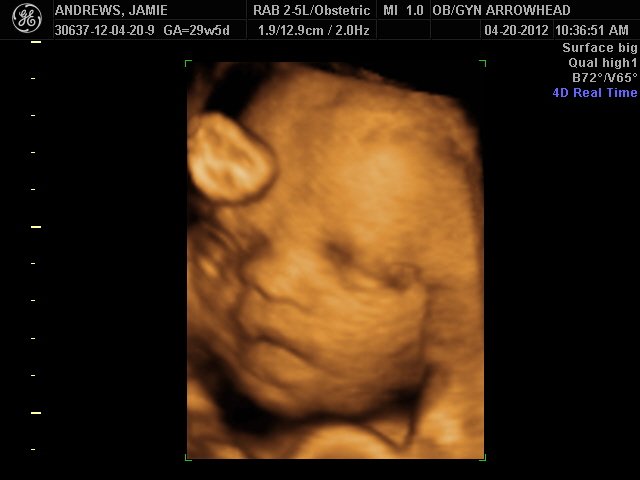

We offer complimentary 3D/4D Ultrasounds to all our OB patients around 30 weeks! The following photos are some examples of our work, shown with permission from our patients.